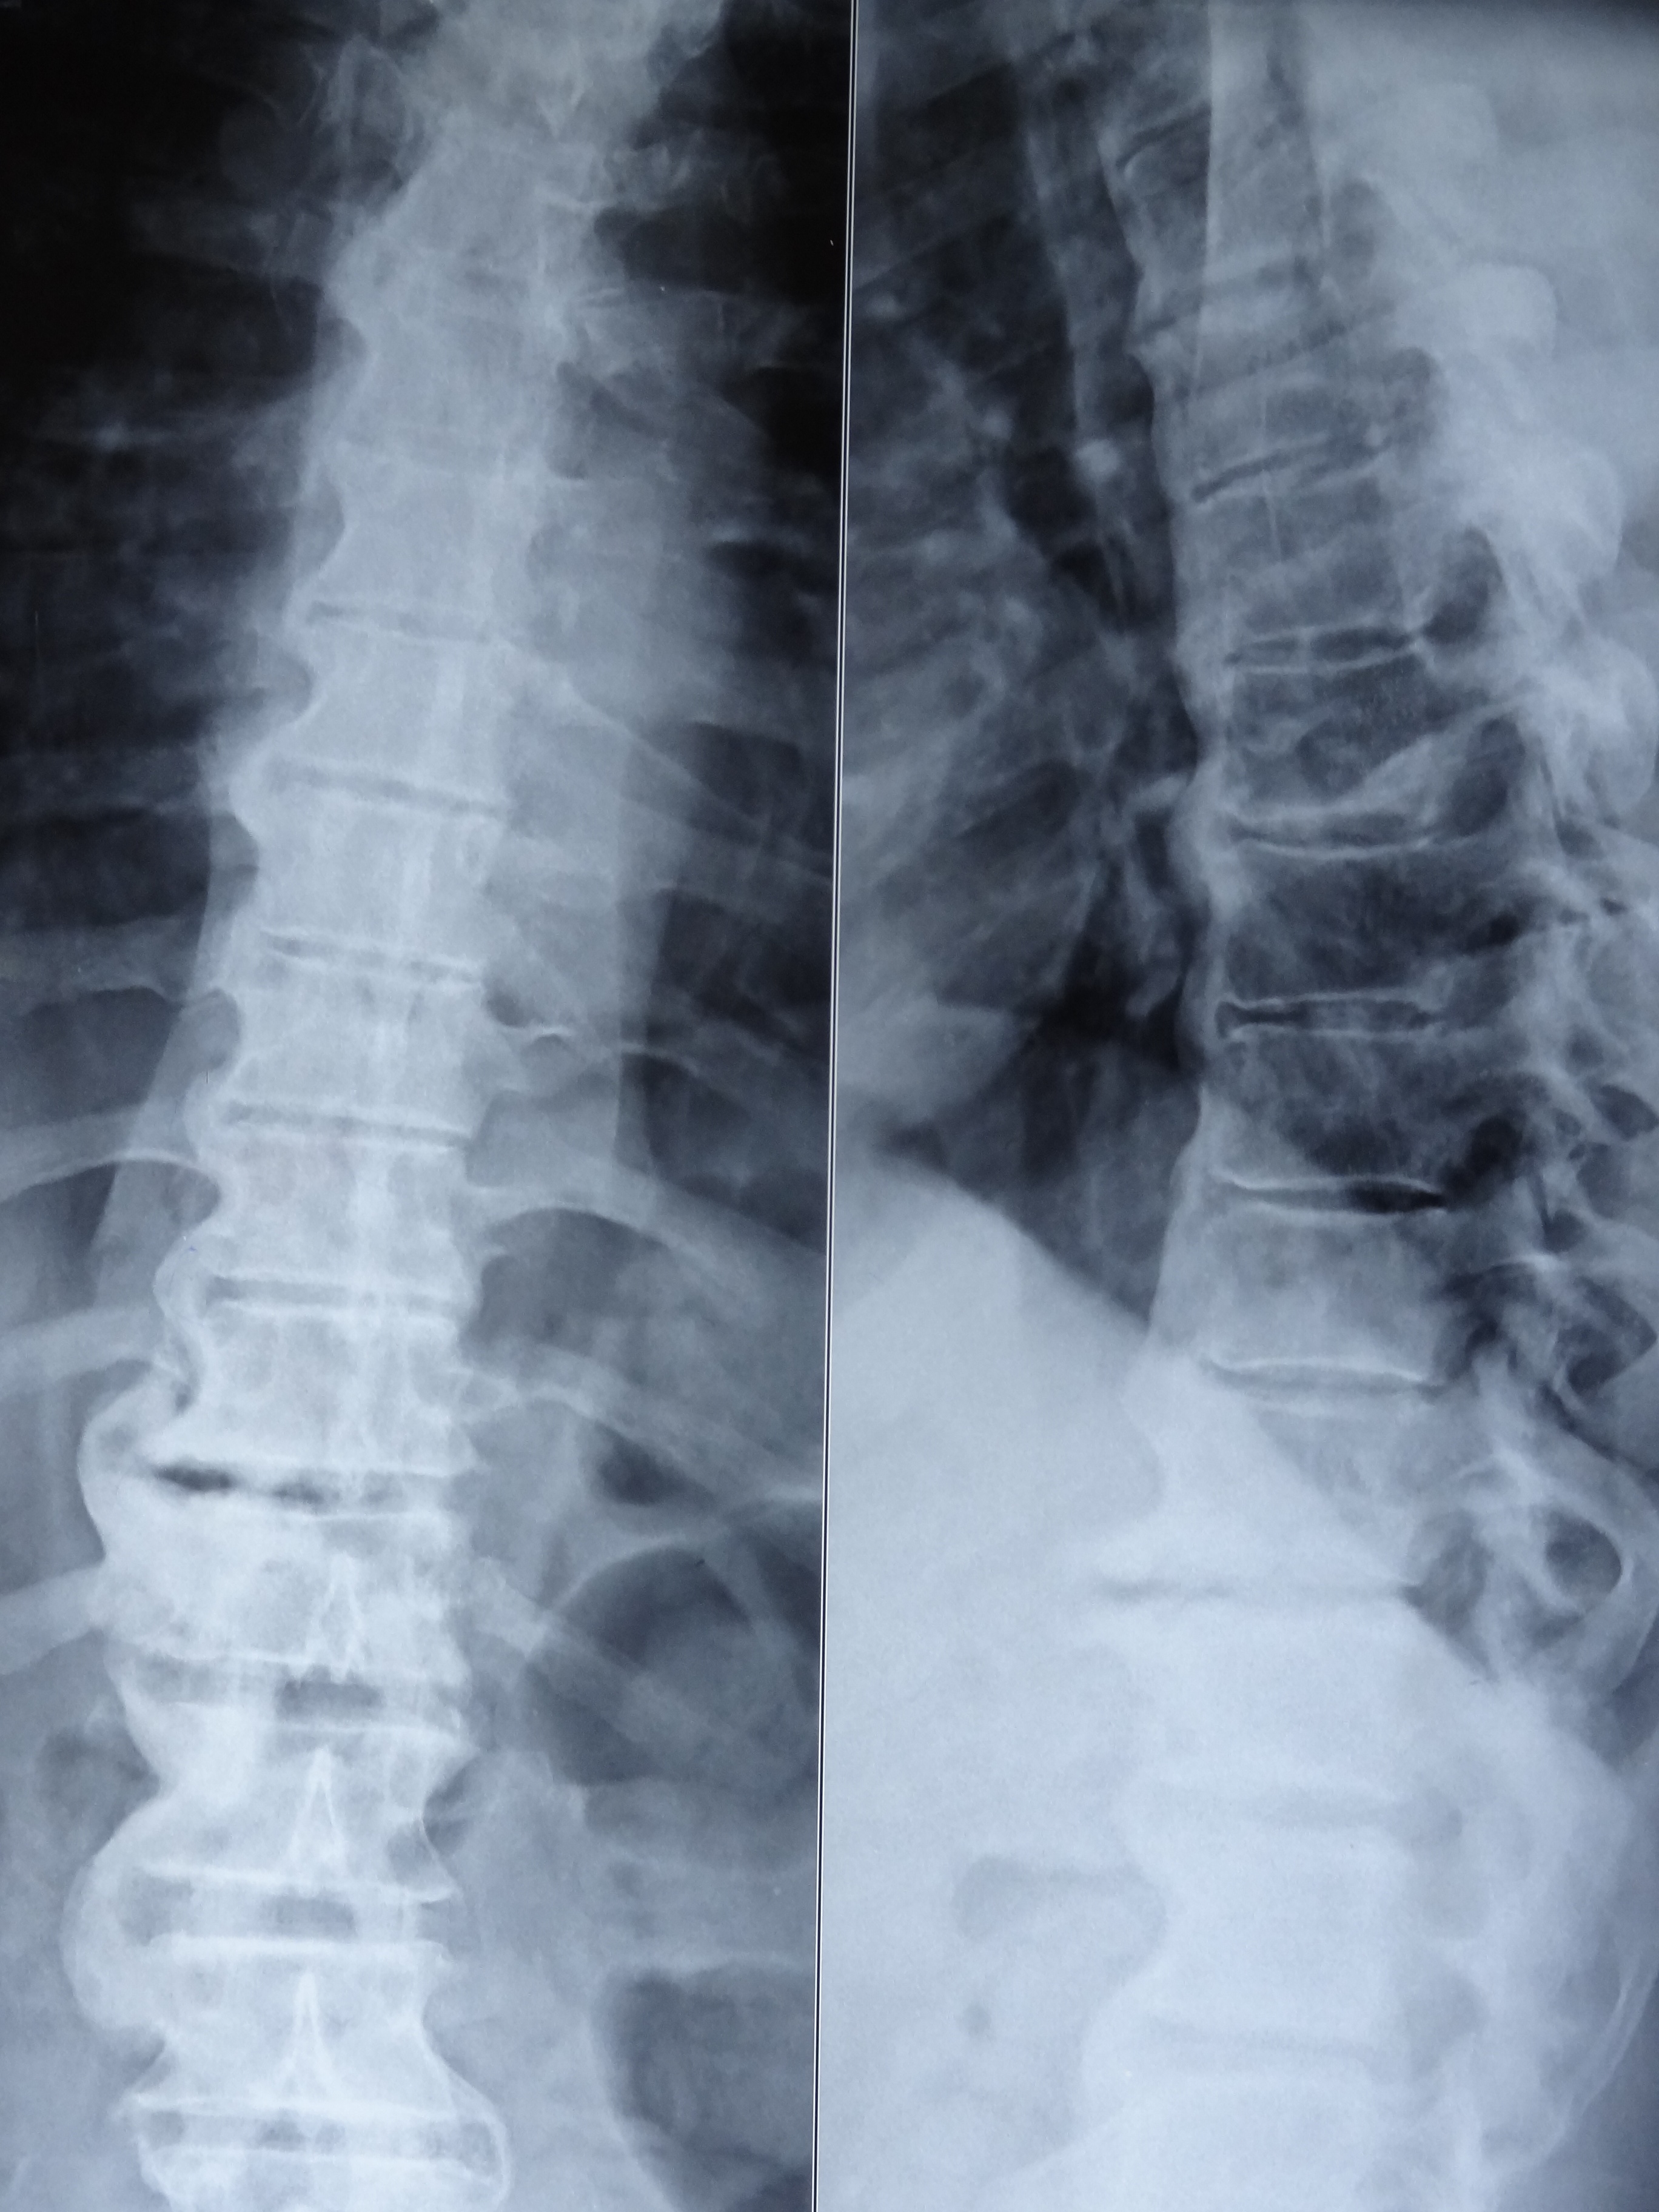

A 70-year-old diabetic and hypertensive male patient visited our clinic with complaints of non-inflammatory back pain since two years. He was heavy built with a BMI of 29 kg/m2. Physical examination revealed limitation of flexion, extension, and lateral flexion of lumbar spine. X-ray of spine revealed flowing calcification of anterior longitudinal ligaments from cervical to lumbar spine with claw osteophytes giving rise to characteristic ‘Melting Wax’ appearance (Panel A: fig A- cervical anteroposterior (AP), fig B- cervical lateral , fig C- lumbar AP , fig D- lumbar lateral) (Panel B: fig E- thoracolumbar AP, fig F- thoracolumbar lateral). Sacroiliac joints were normal (Panel A: fig C- white arrow). The diagnosis was diffuse idiopathic skeletal hyperostosis (DISH or Forestier’s disease) and symptomatic treatment was initiated.